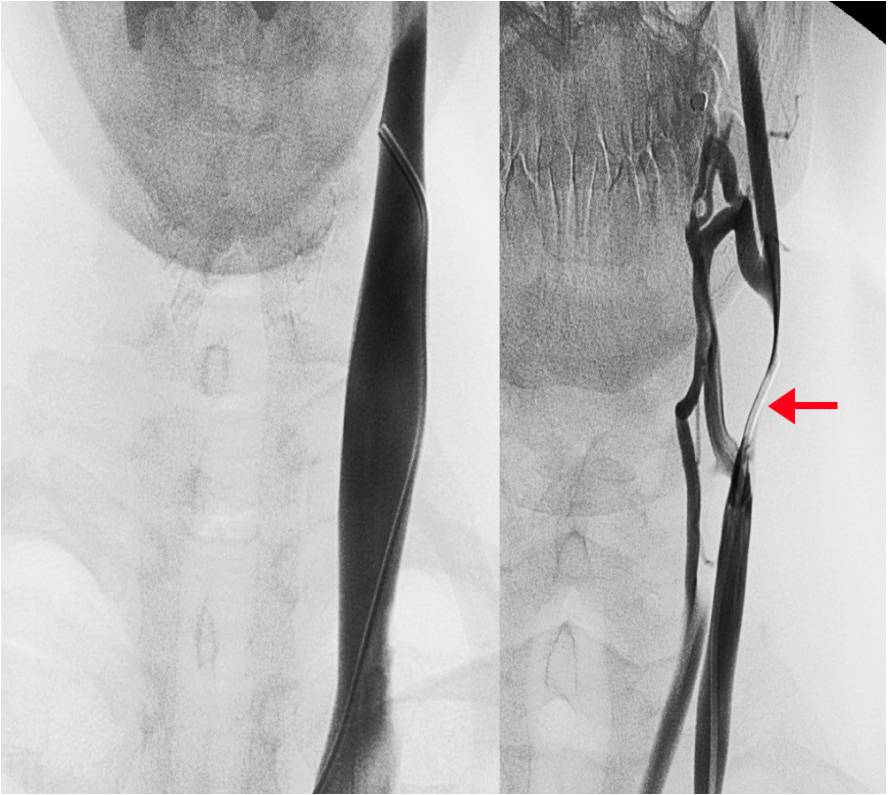

Dida foto a fianco. A sinistra: venografia con catetere della vena giugulare interna nel controllo sano; A destra: Stenosi (indicata dalla freccia) e circoli collaterali attivati in un caso di entrambi studiati per mezzo della venografia con catetere.